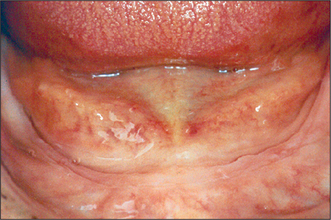

Other anatomical structures may become more prominent with tooth loss. The genial tubercles and their muscle attachments may become prominent in a patient with extensive resorption of the mandible, sometimes compromising denture stability. Maxillary or mandibular tori may also cause instability of a denture, or may be traumatized by it. A prominent fraenum (Fig. 11.3) can displace a denture during function, and may weaken the denture base so that it fractures through flexing.

image

Fig. 11.3 A prominent labial fraenum causes displacement of the denture. If the denture flange is eased to fit round the fraenum, the denture may be weakened. Excision of the fraenum (fraenectomy) is indicated.

Prominent labial fraenum

The flange of a denture may traumatize a prominent labial fraenum or muscle attachment (Fig. 11.3). If the fraenum is relatively small, this may be managed by trimming back the labial or lingual denture flange. However, the denture may be weakened and it might fracture if extensive trimming is undertaken to relieve the fraenum. Excision of the fraenum (fraenectomy) may be indicated to avoid this.